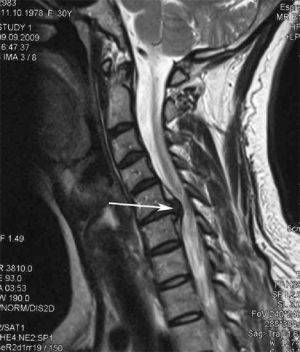

Стенозом позвоночного канала называют уменьшение его размера в передне-заднем направлении, а также уменьшение его ширины. Сужение позвоночного канала в шейном отделе наиболее часто встречается при образовании межпозвонковых грыж, остеофитов (костных разрастаний в позвоночном канале), гипертрофии (утолщении) задней продольной связки, нестабильности позвоночника (Рис.1).

Рис.1. Магнитно-резонансная томография (МРТ) шейного отдела позвоночника в сагиттальной проекции. Стеноз позвоночного канала на уровне С5-С6 позвонков, обусловленный парамедианной секвестированной мп грыжей диска больших размеров (показана стрелкой). Кроме того, на уровне стрелки определяется кифотическая деформация шейного отдела позвоночника (описание см. в тексте).